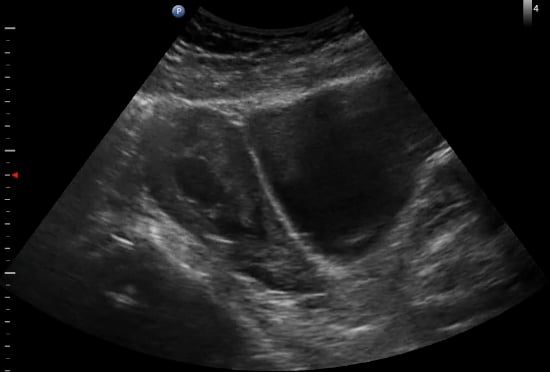

In OBGYN ultrasound, the yolk sac is a crucial early gestational structure, appearing as a small, round, anechoic fluid-filled sac within the chorionic cavity. Typically visible from 5-10 weeks of gestation, its presence confirms an intrauterine pregnancy and is a vital indicator of normal embryonic development. The yolk sac provides early nourishment to the embryo before the placenta fully forms.

Its proper visualization and size are important for dating the pregnancy and assessing viability. Abnormalities in yolk sac appearance, such as irregular shape or absent visualization when expected, can suggest potential complications or early pregnancy failure. Therefore, precise identification and evaluation of the yolk sac are fundamental for accurate diagnostic ultrasound in obstetrics.